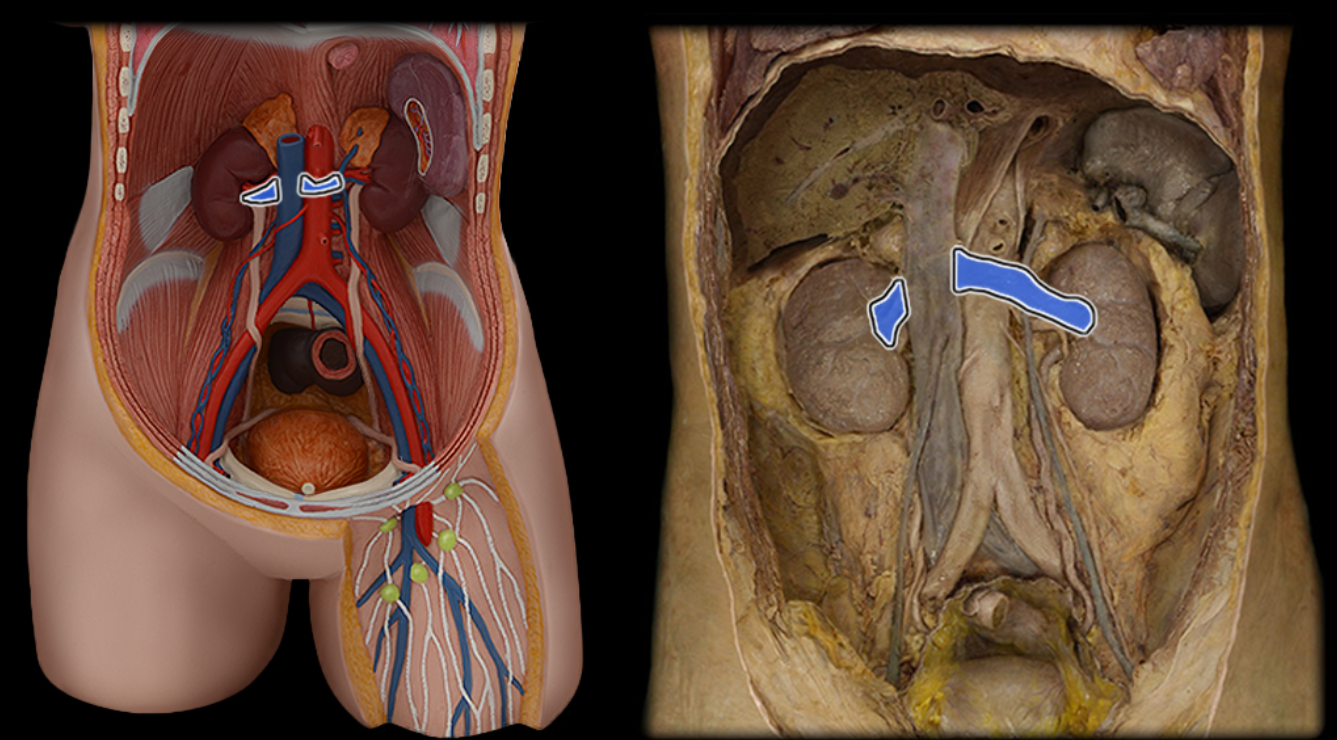

Abdominal aorta

Common iliac a.

Common iliac v.

External iliac a.

External iliac v.

Femoral a.

Femoral v.

Gonadal a.

Gonadal v.

Inferior vena cava

Lumbar a.

Lumbar v.

Renal a.

Renal v.

Superior mesenteric a.